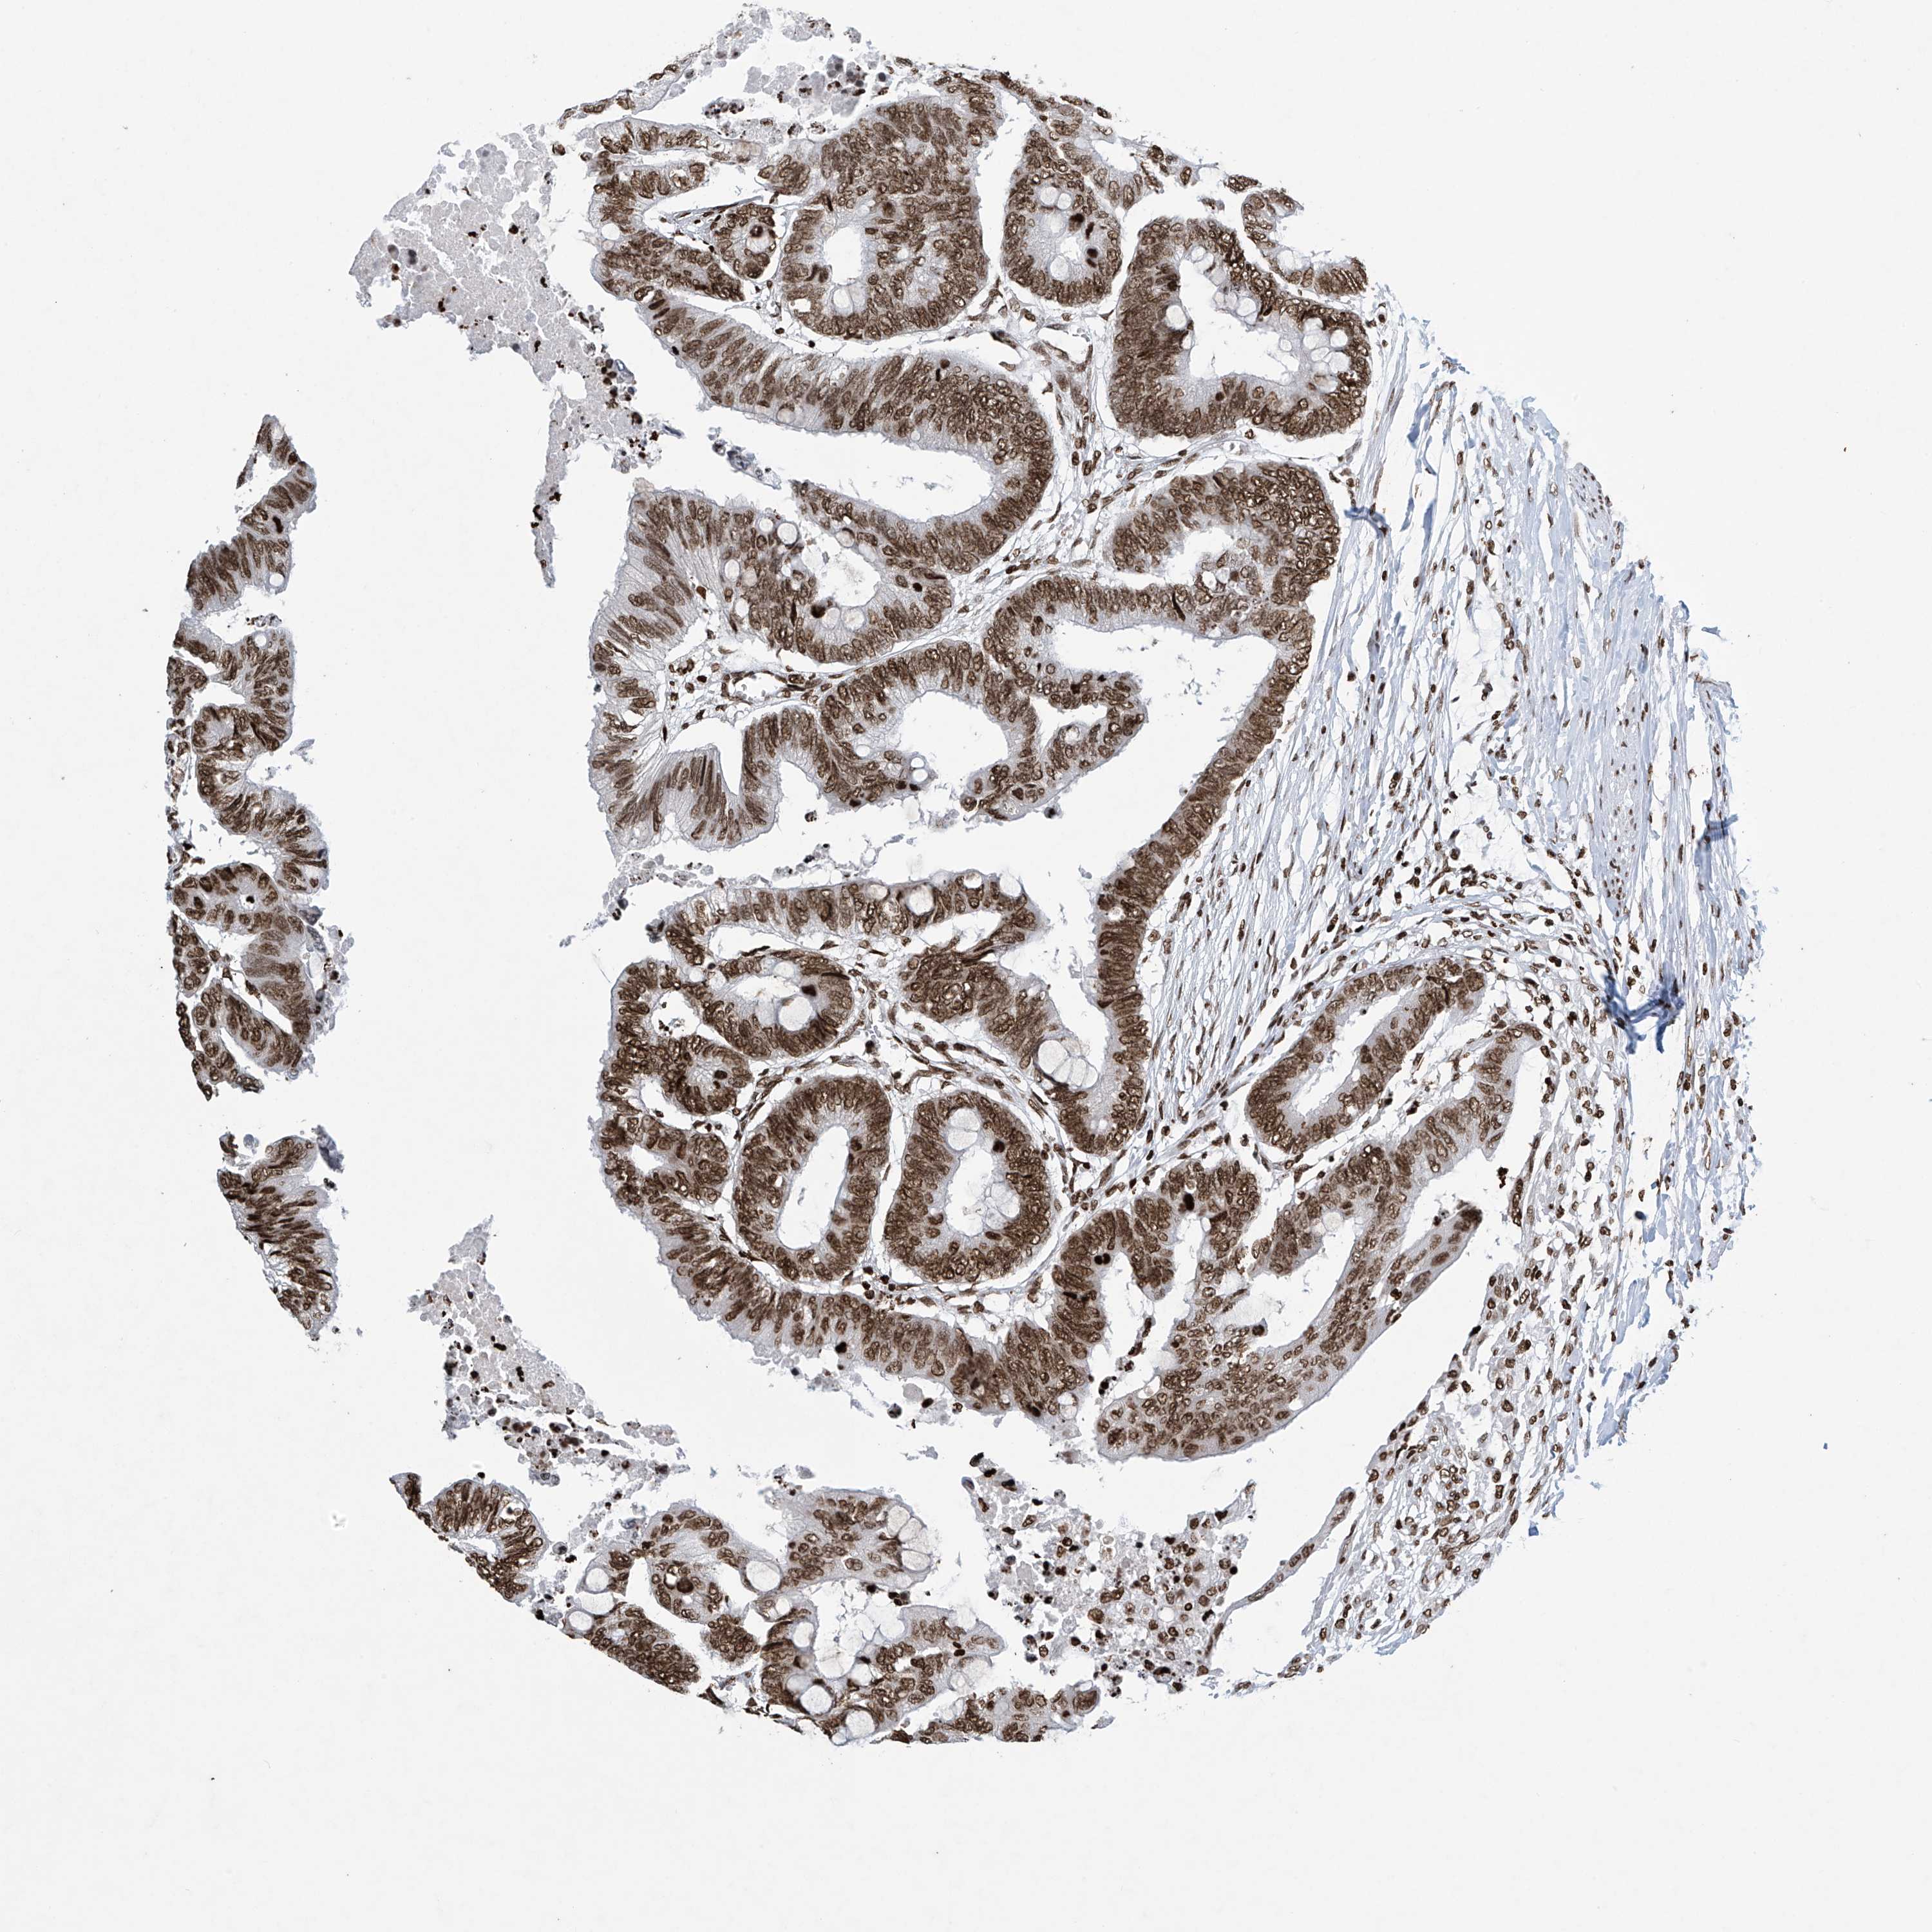

CANCER COLORECTAL CANCER Show tissue menu

Colorectal cancer

Human cancer

Colon adenocarcinoma